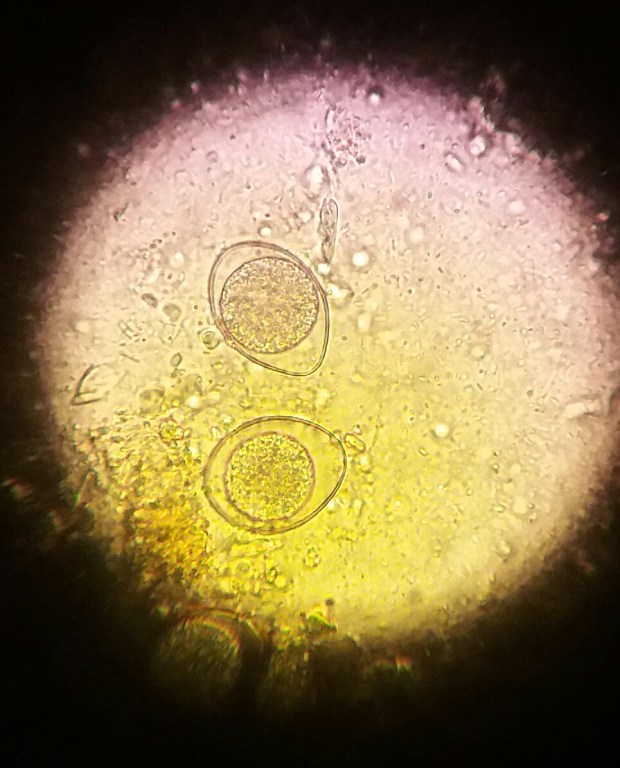

Cuando el cuadro clínico lo recomiende se realizarán análisis de los parámetros adecuados.

Otros los podemos realizar en la propia clínica, para lo que contamos con un área de análisis.